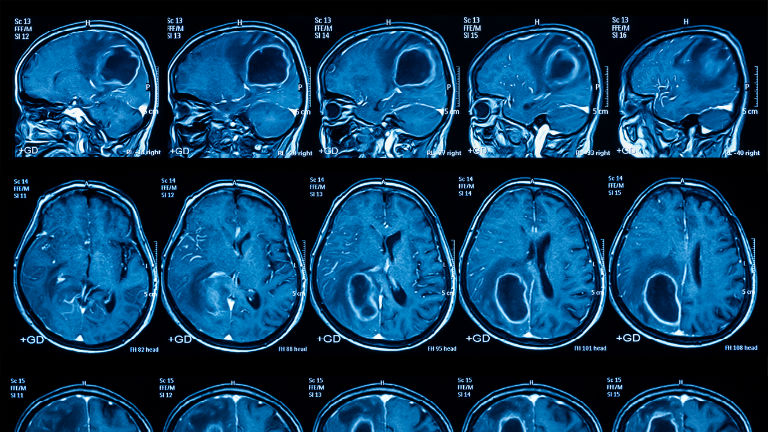

Csodálatos gyógyulás: nyomtalanul eltűnt a kislány agyából a tumor

A menopauzára fogták a fejfájást, kiderült, hogy agytumor

Tojásnyi tumort távolítottak el az agyából – végig ébren volt

Agydaganatot állapítottak meg az Édes élet egyik szereplőjénél